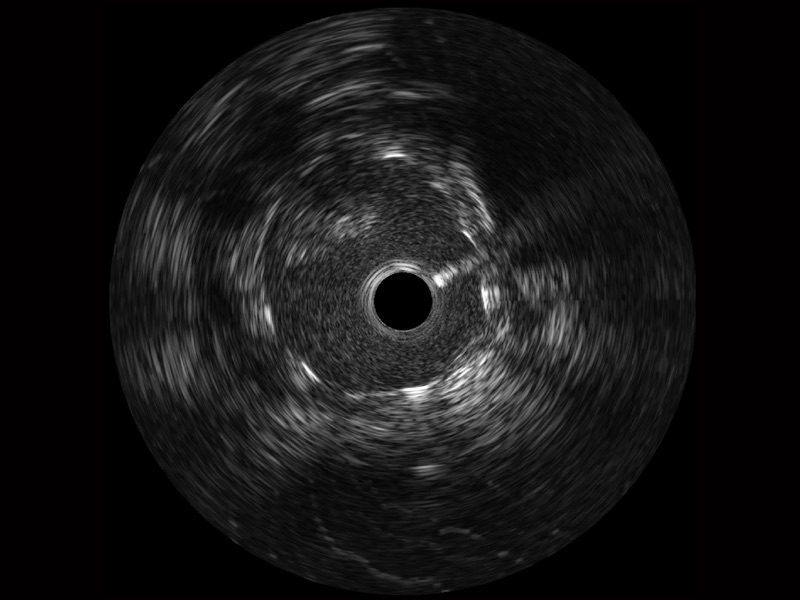

• 16877太阳集团宽频IVUS图像

• 传统IVUS图像

对比传统IVUS导管成像,16877太阳集团宽频IVUS图像的近场支架梁显影更细腻,远场中膜外血管仍清晰可辨,兼顾远中近,兼顾分辨力与穿透深度